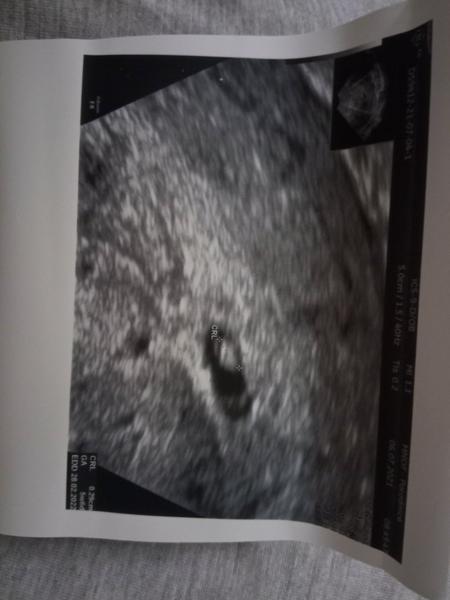

@nazka na utz tohle. Myslím si že je to progres. minulý týden v pátek tam měl doktor to, co mám na profilovém obrázku.

Ahoj všem. Potřebovala bych radu a povzbuzení. Podle mudr z nemocnice bych měly být 6tt+0, hodnota HCG je na 1800 jednotek. Je to málo? Na utz je vidět těhotenský váček i struktury plodu. Je možné že je těhotenství mladší? Chtějí mě poslat na revizi ale podle utz mrňousek roste. Předem děkuji 🙂